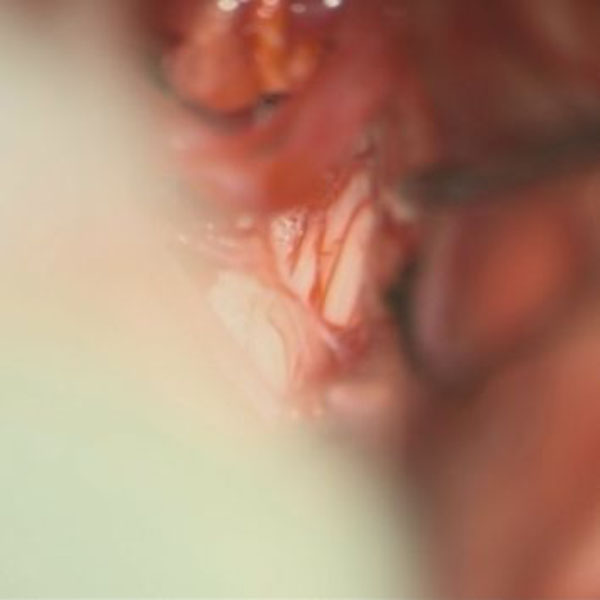

症例 '26年3月

No.

585

手術医師

手術年月

年齢

病名

術式

手術前

減圧前

減圧後

手術後

大阪府の病院

'26年3月

40代

左顔面痙攣

(痙攣をとること)

術後血管撮影